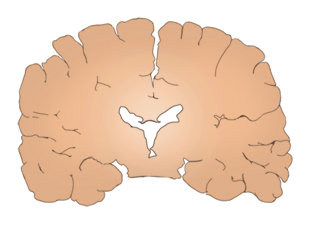

알츠하이머병은 치매를 일으키는 가장 흔한 퇴행성 뇌질환으로, 1907년 독일의 정신과 의사인 알로이스 알츠하이머 (Alois Alzheimer) 박사에 의해 최초로 보고되었다. 알츠하이머병은 매우 서서히 발병하여 점진적으로 진행되는 경과가 특징적이다. 초기에는 주로 최근 일에 대한 기억력에서 문제를 보이다가 진행하면서 언어기능이나 판단력 등 다른 여러 인지기능의 이상을 동반하게 되다가 결국에는 모든 일상 생활 기능을 상실하게 된다. 알츠하이머병은 그 진행과정에서 인지기능 저하뿐만 아니라 성격변화, 초조행동, 우울증, 망상, 환각, 공격성 증가, 수면 장애 등의 정신행동 증상이 흔히 동반되며 말기에 이르면 경직, 보행 이상 등의 신경학적 장애 또는 대소변 실금, 감염, 욕창 등 신체적인 합병증까지 나타나게 된다. 현미경으로 알츠하이머병 환자의 뇌 조직을 검사하였을 때 특징적인 병변인 신경반(neuritic plaque)과 신경섬유다발(neurofibrillary tangle) 등이 관찰되고, 육안 관찰 시에는 신경세포 소실로 인해 전반적 뇌 위축 소견이 보인다. 이러한 뇌 병리 소견은 질병 초기에는 주로 기억력을 담당하는 주요 뇌 부위인 해마와 내후각뇌피질 부위에 국한되어 나타나지만 점차 두정엽, 전두엽 등을 거쳐 뇌 전체로 퍼져나간다. 이러한 뇌 병리 침범 부위의 진행에 따라 초기에는 기억력 저하가 주로 나타나다가 진행됨에 따라 점진적인 경과를 보이면서 임상 증상이 다양해지고 점점 더 심해지게 되는 것이다. 알츠하이머병의 호발 연령은 65세 이후이나 드물지만 40, 50대에서도 발생한다. 발병 연령에 따라 65세 미만에서 발병한 경우를 조발성(초로기) 알츠하이머병, 65세 이상에서 발병한 경우 만발성(노년기) 알츠하이머병으로 구분할 수 있다. 조발성 알츠하이머병은 비교적 진행 속도가 빠르고 언어기능의 저하가 비교적 초기에 나타나는 등의 특징을 보이는 반면, 만발성 알츠하이머병의 경우 상대적으로 진행이 느리고 다른 인지기능 저하에 비해 기억력의 손상이 두드러진다는 보고도 있으나 근본적으로 두 연령 구분에 따른 병리 소견의 차이는 없으므로 동일 질병으로 간주된다.

알츠하이머병 노인과 정상 노인의 뇌 모습

정상 노인의 뇌 단면

알츠하이머병 노인의 뇌 단면